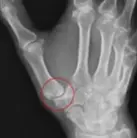

母指CM関節がずれている。

『母指CM関節症』が進んだ状態。ゴツゴツとした見た目に。